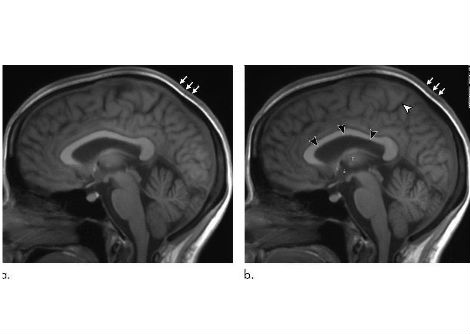

إذا استمرت الجمجمة البشرية في التطور ، يتوقع العلماء أن تصل إلى مرحلة الشباب من حيث أبعاد الجمجمة ، مما قد يؤدي إلى وجه أصغر ، مع مدارات عين أكبر نسبيًا ، وذقن ذات أبعاد أصغر ، وقبة كروية أكثر تطورًا.

سيكون هذا متوقعًا إذا حدثت عملية تُعرف باسم "استدامة المرحلة اليرقية" ، مما يعني أن الناس سيحتفظون بالفعل بمظهرهم اليافع عند بلوغهم سن الرشد .

وجه أصغر ، جمجمة أكبر ، وجه المستقبل؟

يعتقد العلماء أن وجه المستقبل سيبدو مثل هذا.

بعبارة أخرى ، يرى الخبراء أن رجل المستقبل سيكون على الأرجح وجهًا أصغر حجمًا وجمجمة أكبر مقارنةً بالناس اليوم .